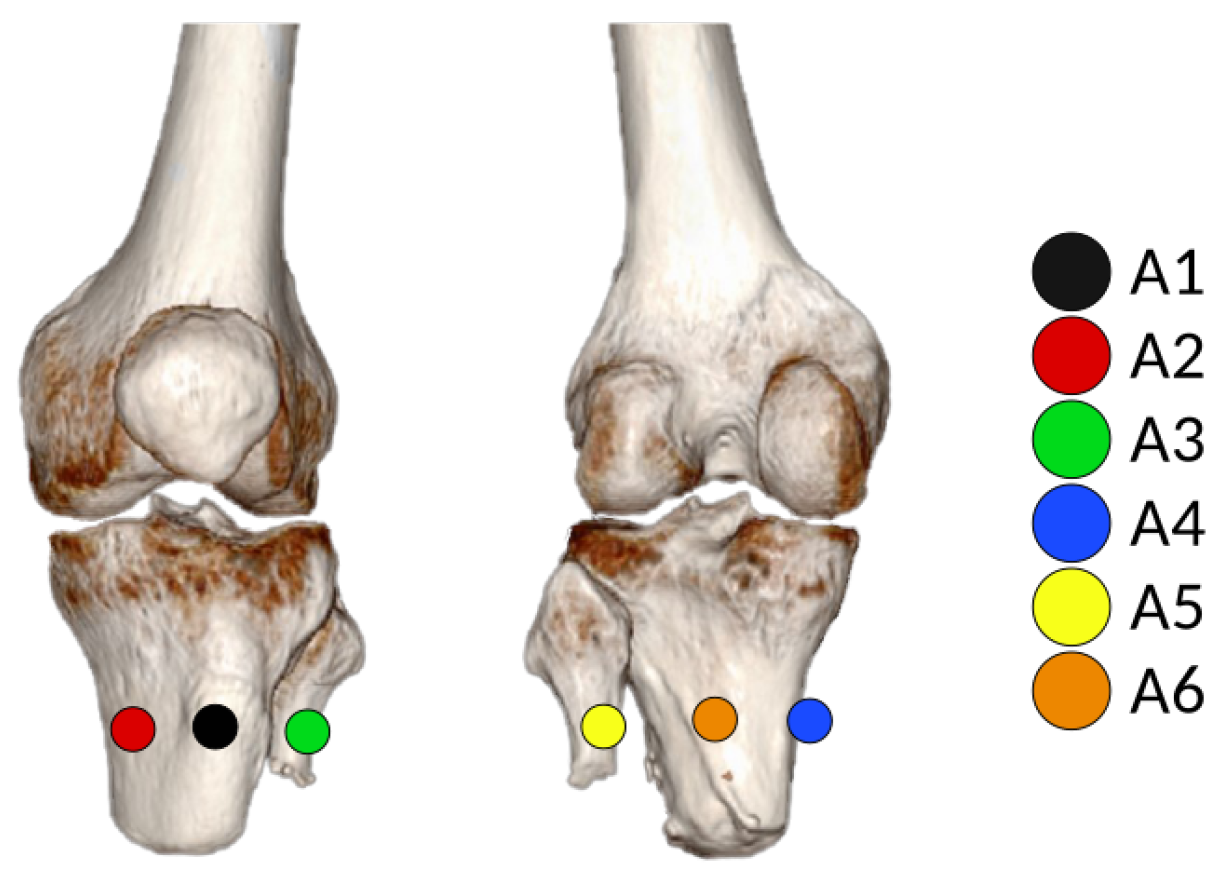

2.3. Croi Location